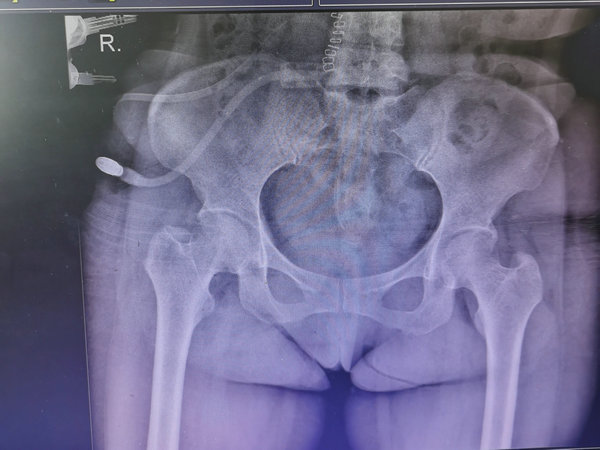

术后腹透导管的位置